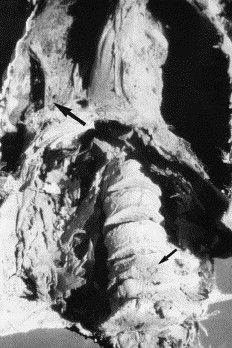

The bacterium targets the lungs with symptoms of fever, tiredness, and a cough. Later in the infection, the bacterium quickly escalates those symptoms, resulting in coughing blood, chest pain, and weight loss. Tuberculosis leaves scars on the lungs, which has helped researchers identify cases of it in ancient human remains.

We have found tuberculosis in mummies that are over 4,000 years old, and researchers have discovered tuberculosis in Neolithic remains, which makes tuberculosis at least 9,000 years old! In 2023, over 10 million people were infected, with over 1 million dying.